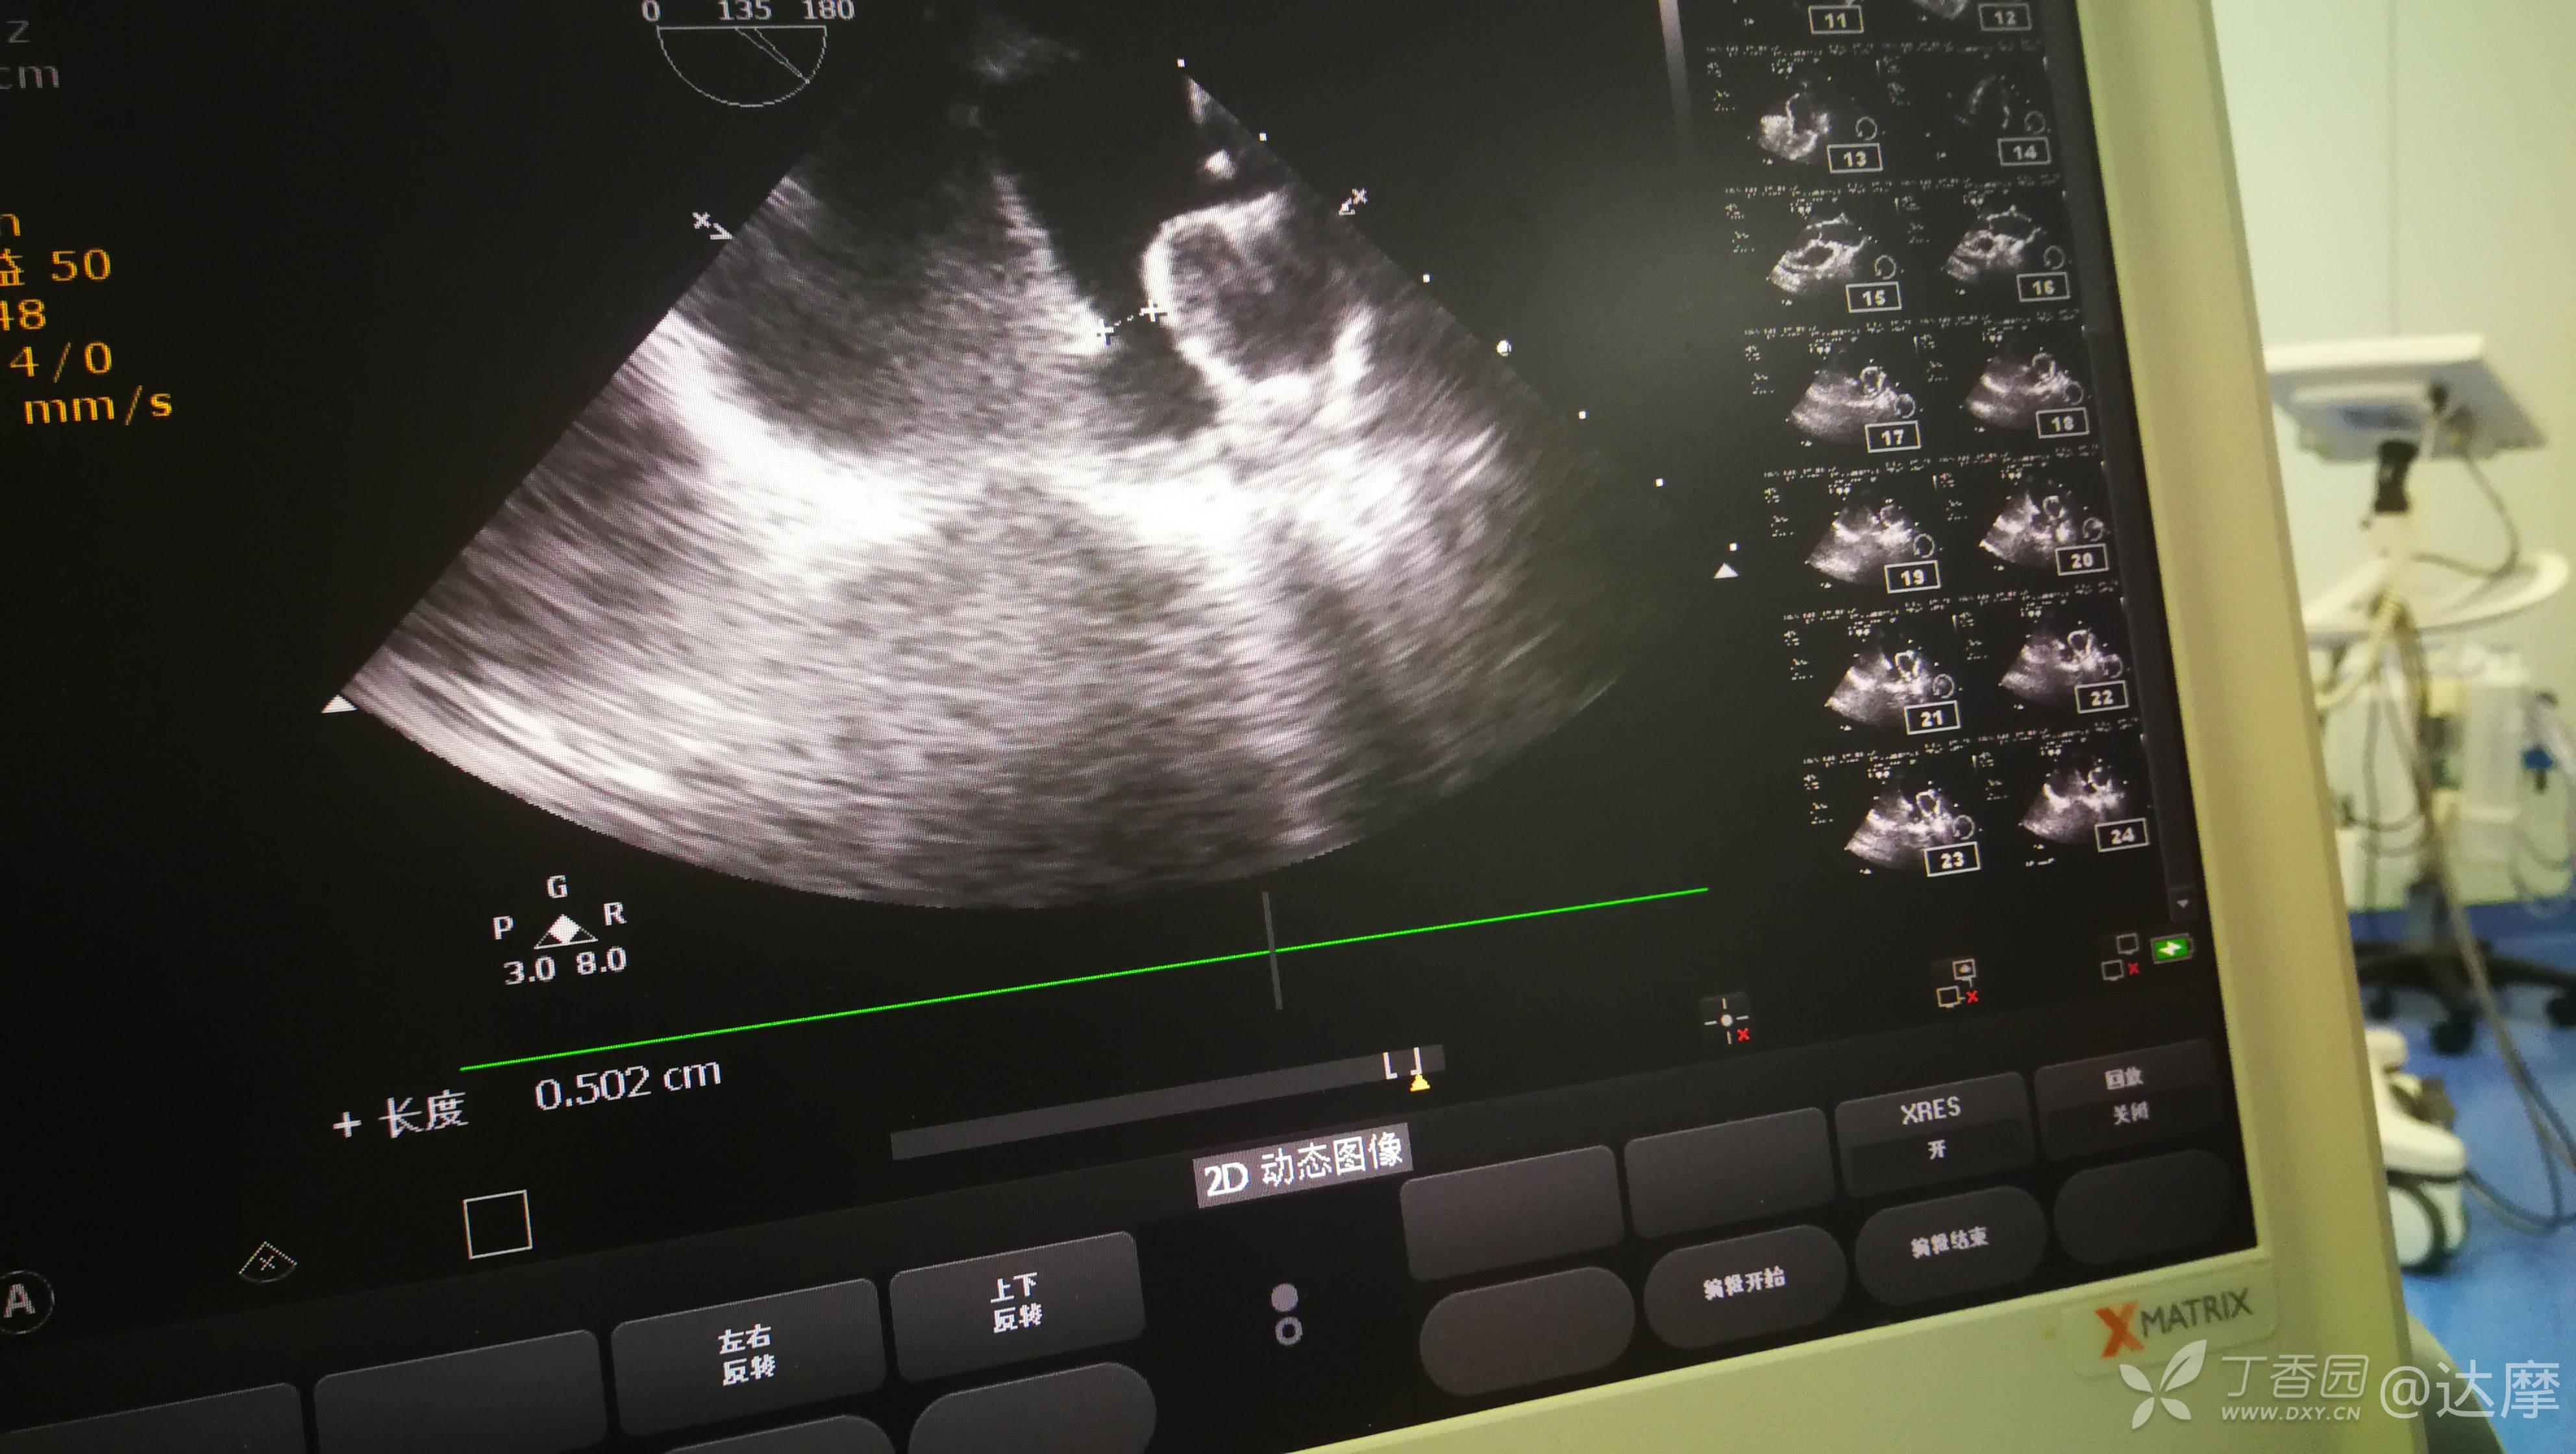

选择了当前最大的封堵器,术中尝试封堵情况如下: